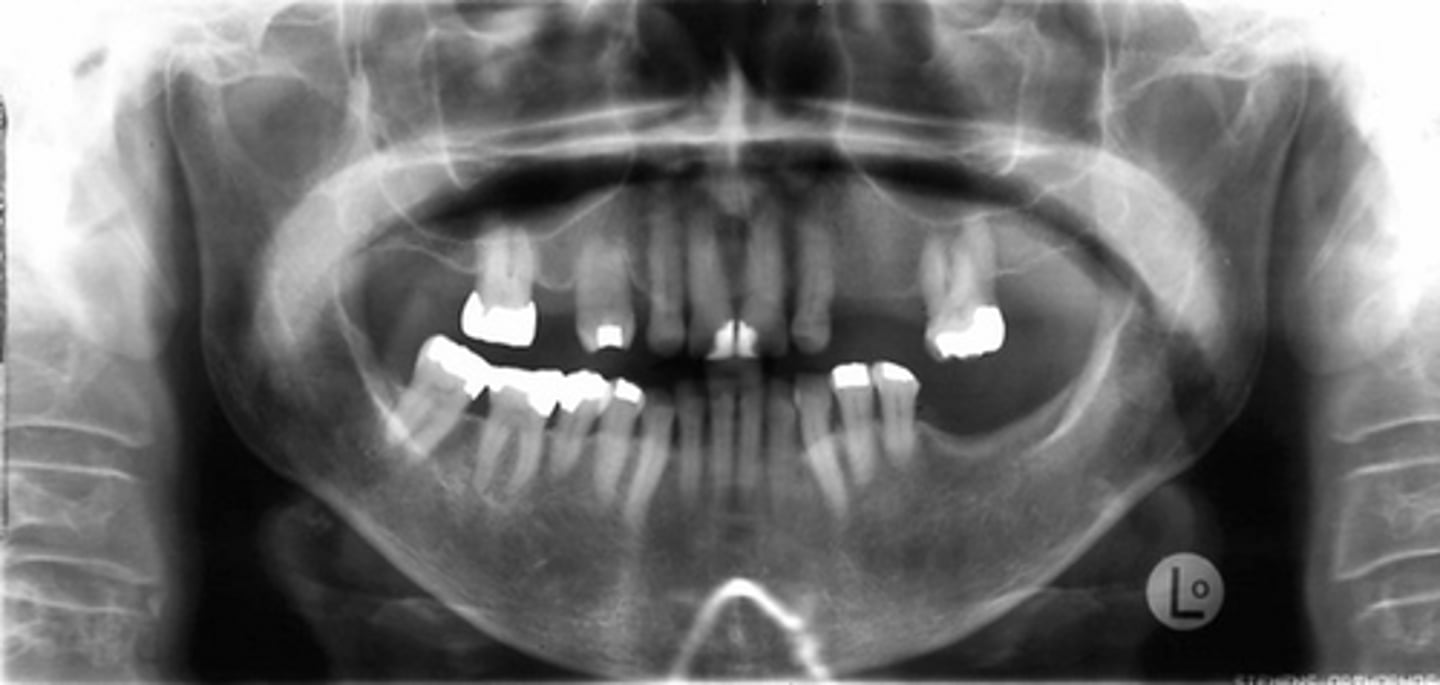

Thalassemia

This pathology is due to a genetic defect that causes RBC's with reduced hemoglobin content.

True or False. Thalassemia results in hyperplasia of the bone marrow and will radiographically looks similar to sickle cell anemia.

Sickle cell anemia or Thalassemia (both with have enlarged marrow spaces)

These enlarged marrow spaces are indicative of